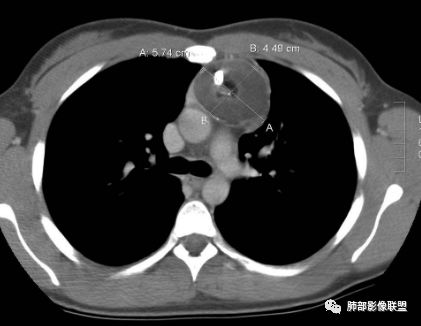

水晶石头:患者老年男性,发现皮肤粘膜黄染5天,右肺占位1天。

胸部CT:右肺中叶内侧段紧邻心脏实性结节,边缘光滑,边界清楚,宽基底与胸膜相连,内可见不规则钙化,钙化内见点状低密度影,增强中度强化,综合考虑良性病变。畸胎瘤可能大,鉴别胸膜孤立性纤维瘤及胸腺瘤。

王秀仙:右侧前纵隔肿块,边缘分叶,周围肺组织推移,宽基底与纵隔胸膜相连,可见胸膜尾征,密度不均,病灶中心可见斑块状钙化,右侧内乳动脉位于病灶前外侧并略增粗,实性成分明显强化,考虑纵隔畸胎瘤,鉴别胸腺瘤。

右侧前纵膈肿块,边缘分叶,病灶中心可见斑块状钙化,实性成分明显持续强化,考虑胸腺瘤。